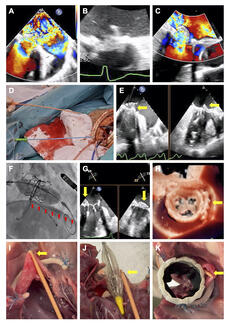

The authors propose the Unilateral Folding of the anterior mitral valve leaflet (UNIFOLD) as a novel mechanism to prevent left ventricular outflow tract obstruction.